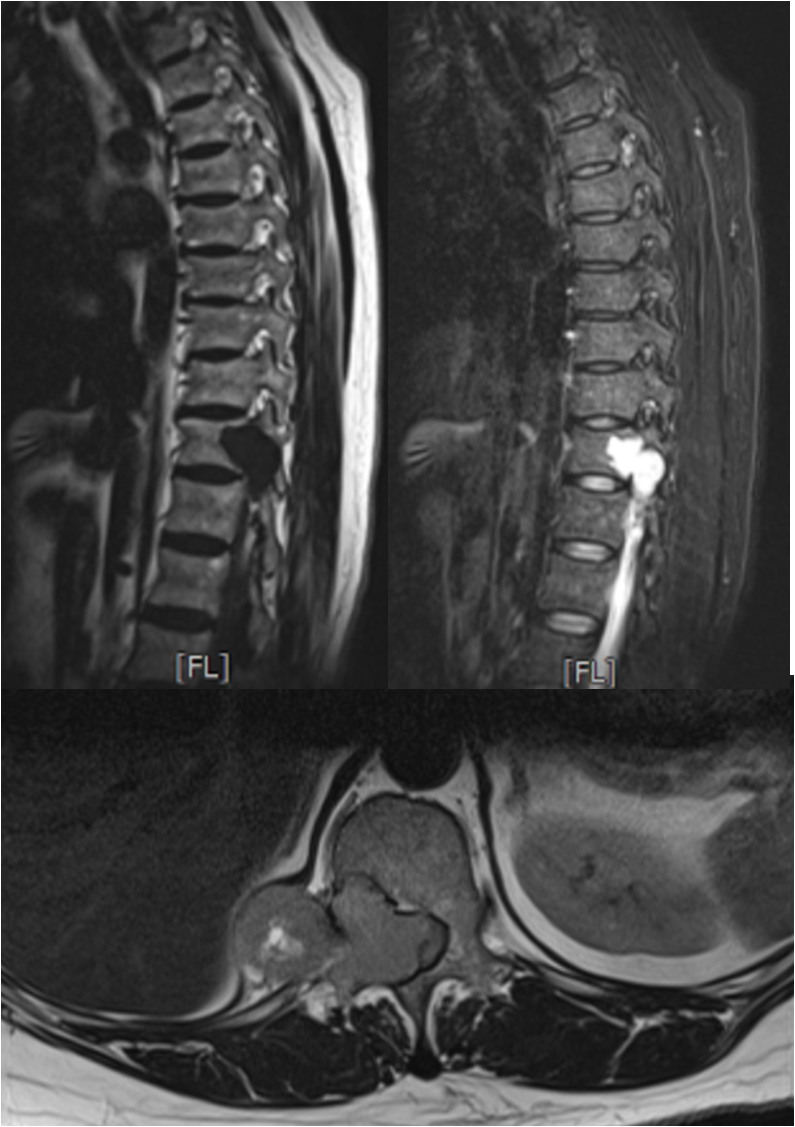

四个月前,这位患者因右侧小腿无力,辗转于西安多家医院寻求治疗,但均未能获得显著改善。随着病情恶化,她的右下肢无力症状逐渐加重,并导致无法行走。患者来到我院骨科中心门诊,秦杰副主任医师接诊后,经过细致的查体,发现患者双侧下肢感觉减退,右下肢的屈髋、伸膝及足背伸跖屈肌力均显著下降(0-1级)。鉴于病情严重,秦杰副主任医师果断将患者收治入院,并进行了详尽的神经系统检查。影像学结果显示,患者胸11-12椎体平面椎管内存在巨大占位,严重压迫脊髓,并已穿过右侧椎间孔向右侧胸腔生长。幸运的是,全身检查并未在其他部位发现原发肿瘤。

明确病情后,与患者家属充分沟通交流了病情,病人椎管内占位体积庞大且生长迅速,若不及时手术挽救残余神经功能,患者将面临双下肢瘫痪,生活质量将急剧降低。然而,手术风险同样巨大,肿瘤不仅巨大且位置深邃,与脊髓关系紧密,椎管侵占率超过了80%以上,稍有不慎便可能损伤脊髓和大血管,危及生命。经过多学科团队协作(MDT)深入讨论和充分的围术期准备,王栋教授带领团队为患者制定了周密的治疗方案。

在患者及家属的全力支持与配合下,手术由王栋主任主刀,秦杰副主任医师、李京主治医师和邹宇佳规培医师协助,麻醉科李芳组长、牛晓莉副主任医师实施麻醉,手术室赵丽燕护士长、古茹副护士长和胡佩莹护士的配合协助。手术过程中,发现肿瘤呈不规则形,向椎管内、腹膜后、椎管后方等多个方向生长,最大直径近12cm。团队成功实施了胸椎椎管内占位切除术和胸椎椎弓根钉内固定术,完整切除了肿瘤既解除了脊髓所受的压迫,又重建了脊柱的稳定性。术后,科室与康复医学科紧密合作,为患者制定了个性化的康复治疗计划,并在骨二科李珂护士长、陈静副护士长和崔凤主管护师的精心指导下进行康复锻炼。